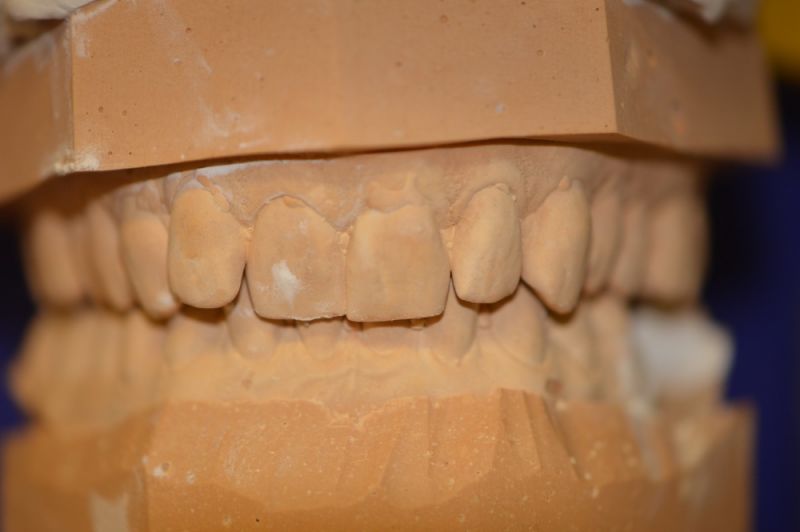

Es läuft dfas Nachweisverfahren einer CMD unter Einsatz eines adjustierten Aufbissbehelfs.

Deutlich erkennbar die Nonokklusion in neuromuskulär zenmtrierter Bisslage